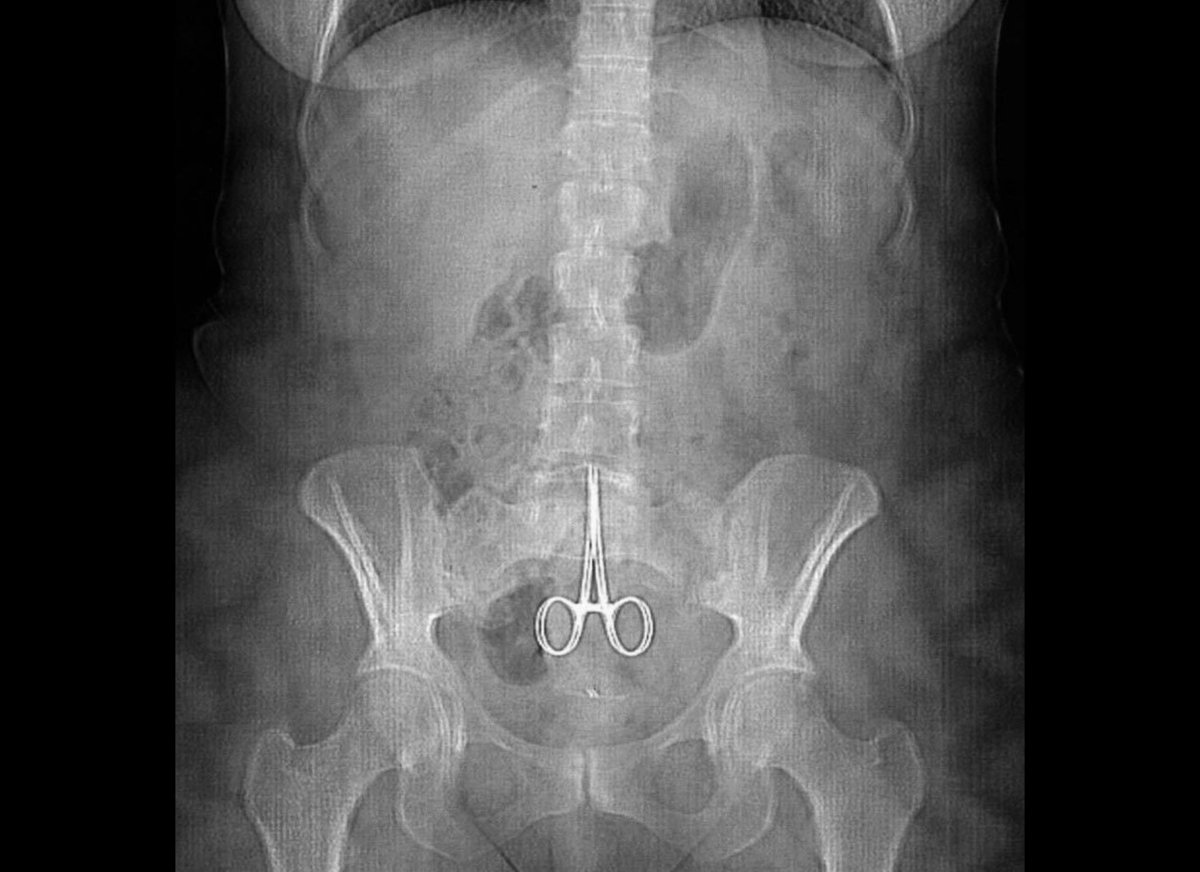

Необычные находки: инородные тела на рентгенограмме брюшной полости